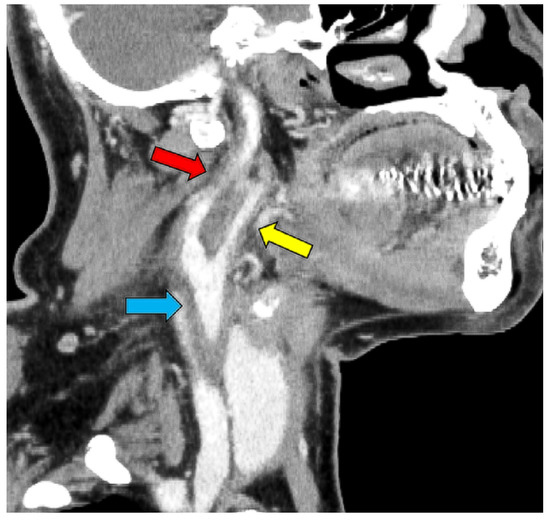

2. Case Presentation

| Shimada et al. (this case) | M | 65 | HTN | Fever and right cervical pain | 3 weeks | Aortic arch to right common carotid artery and right internal carotid artery | CT | 280 | 63 | 18.3 | 24 | None | 11 days | - | Discharge |